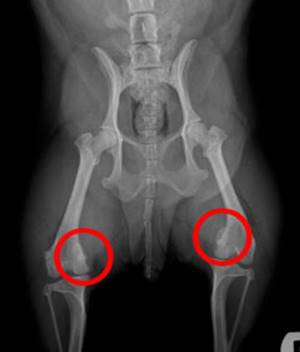

Повреждения коленного сустава представлены в виде вывиха или подвывиха голени, и вывиха надколенника. Этиологическим фактором подобных изменений в колене может быть травмирование, а в некоторых вариантах артроз.

Диагностика осуществляется в условиях травматологического отделения и предусматривает:

- рентгенографическое исследование на предмет целостности кости;